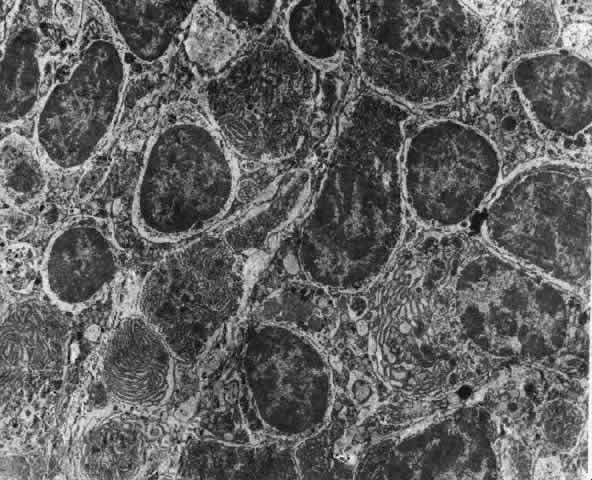

What is clinically represented solely by inflammation and edema is histopathologically a granulomatous lesion of the sclera, the center of which consists largely of plasma cells, lymphocytes, and mast cells (Figs. 21 through 23). Foster and colleagues have identified the cellular subsets and glycoproteins in both necrotizing and non-necrotizing scleritis.22 This shows an active T-cell inflammatory response with a high CD4/CD8 ratio and increased HLA/DR and CD14, indicating a macrophage-induced response that would lead to granuloma formation. Remote from the granuloma, the fibrocytes of the sclera become activated, the proteoglycan adjacent to them becomes altered, and the collagen fibrils of the sclera become unraveled (Figs. 23 and 24). These changes appear to take place prior to the invasion of the stroma by cells of the granuloma.20 The vessels in and around the necrotic area show medial necrosis and perivascular cuffing with lymphocytes, and endothelial swelling with microvascular occlusion. Ninety-six percent of the specimens examined by Foster and associates show a microangiopathy characterized by a neutrophil infiltrate in and around the vessel wall.22–23 This is most obvious at the center of the lesion where there may be occlusion of the vessel, thrombosis, or even aneurysm formation (Fig. 25). From these pathologic investigations, clinical observations, animal experiments, and the results of fluorescein angiography, it would appear that the scleral inflammation is initiated either by trauma (be it accidental or surgical)23–25 or by bacterial or viral infection. If circulating immune complexes are present because of the poor blood flow, they become precipitated in and around the vessel walls in the area of inflammation. In other patients, a persistence of tissue damage will lead to autoimmunization. Damage to the endothelial cells of the microvasculature leads to changes within the vessels detectable on angiography and to catabolic changes in the surrounding tissues. These changes, in turn, allow the granulomatous response that is seen in histopathologic sections, the first detectable change being in the scleral fibrocytes and the proteoglycan and collagen remote from the site of cellular infiltration.

Fig. 22. Electron micrograph of an area of active scleritis showing the plasma cell infiltrate suggestive of an immune response. Note aggregated plasma cells, with the characteristic whorled rough endoplasmic reticulum, in the process of degeneration, releasing organelles and nuclear debris into the extracellular matrix. (Uranyl acetate and lead citrate. X3000) (Courtesy of Dr. R. Tripathi)